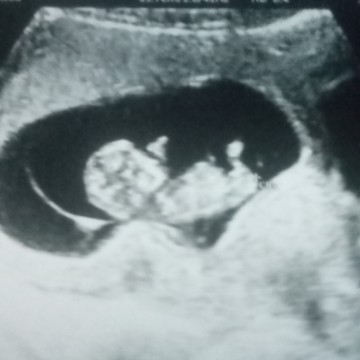

รูปนี้ซาวตอน11wค่ะ ตอนนี้12 แล้ว 💗💗